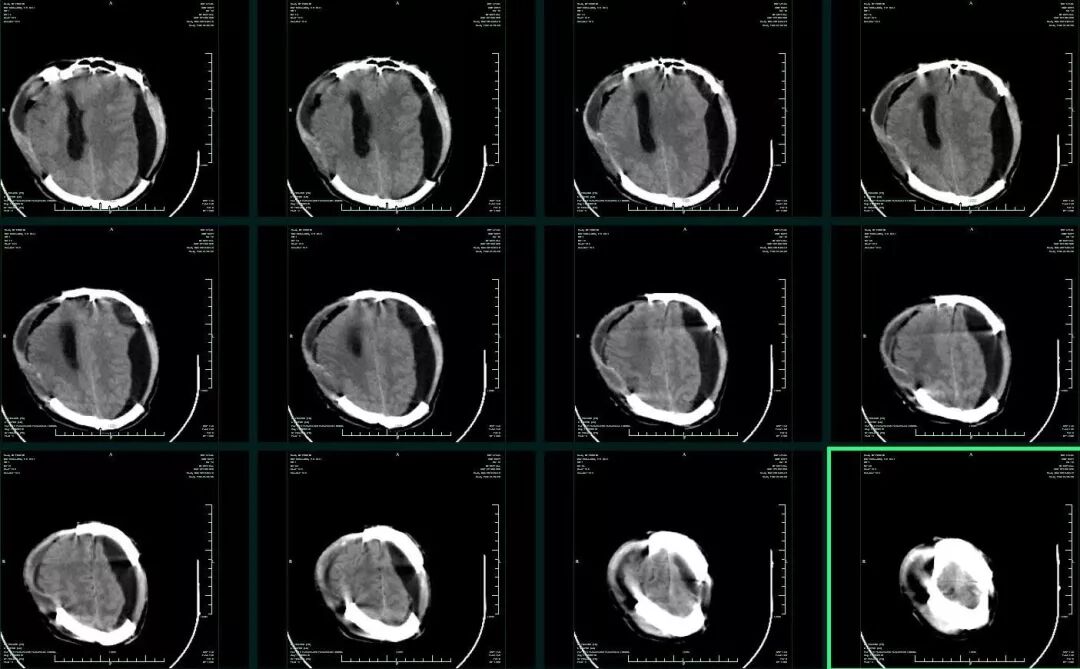

术后一周因右侧颅骨缺损处膨隆加重,复查CT示双侧硬膜下积液,左侧明显(图4),虽反复硬膜下积液抽吸和腰大池持续引流,但积液始终存在,意识状况也逐渐下降,出现深昏迷,GCS4分,左侧瞳孔0.35cm,右侧瞳孔0.2cm,对光反射均消失。一月后CT复查,硬膜下积液如前,左侧呈顽固性硬膜下积液。同时可见左侧额叶脑组织局限性粘连征象(图5)。

图4. 双侧血肿清除+去骨瓣减压术后1周CT提示左侧硬膜下积液,中线右偏。